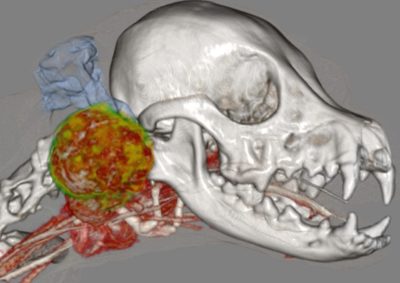

腫瘍外科 注意 ボタンをクリックした先に、治療中および手術中の画像が説明で使用されている場合がございます。 そのような画像に弱い方は閲覧なさらないようお願いいたします。 腫瘍外科 犬の甲状腺癌 軟部組織外科腫瘍外科 唾液腺癌 Salivary gland carcinoma 軟部組織外科腫瘍外科 胃部分切除術・ビルロートI 腫瘍外科 MLO 多小葉性骨腫瘍 腫瘍外科 軟部組織肉腫 G3 軟部組織外科腫瘍外科 直腸プルスルー 内科腫瘍外科 尾状葉乳頭突起に限局した高分化型肝細胞癌 内科腫瘍外科 猫の消化管型リンパ腫(腸穿孔を伴う) 腫瘍外科救急・集中治療 腹腔内出血 内科腫瘍外科救急・集中治療 細菌性腹膜炎 腫瘍外科 肝臓原発血管肉腫 腫瘍外科 犬の原発生肺癌(左) <1234567> 症例カテゴリー 放射線治療整形外科軟部組織外科脳神経外科内科腫瘍外科救急・集中治療リハビリテーション科腫瘍内科内視鏡科脳神経科呼吸器外科中医・漢方猫の腎移植循環器科